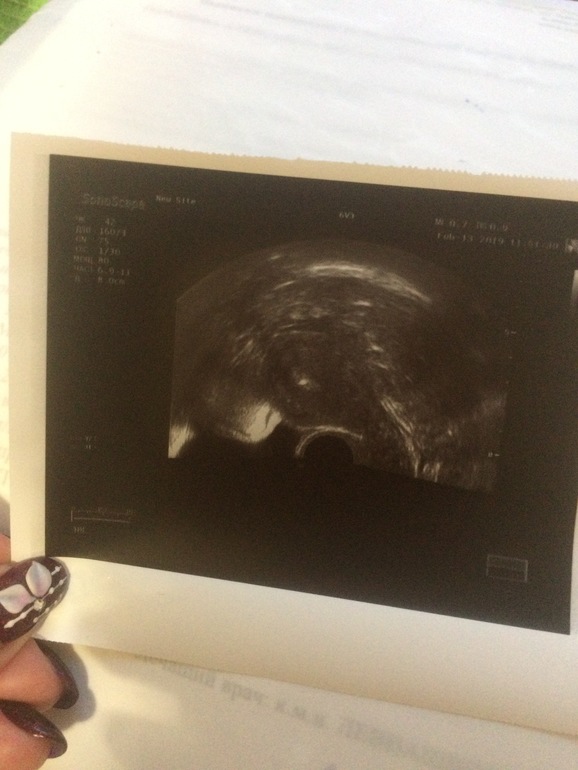

Состоялся крио-перенос .